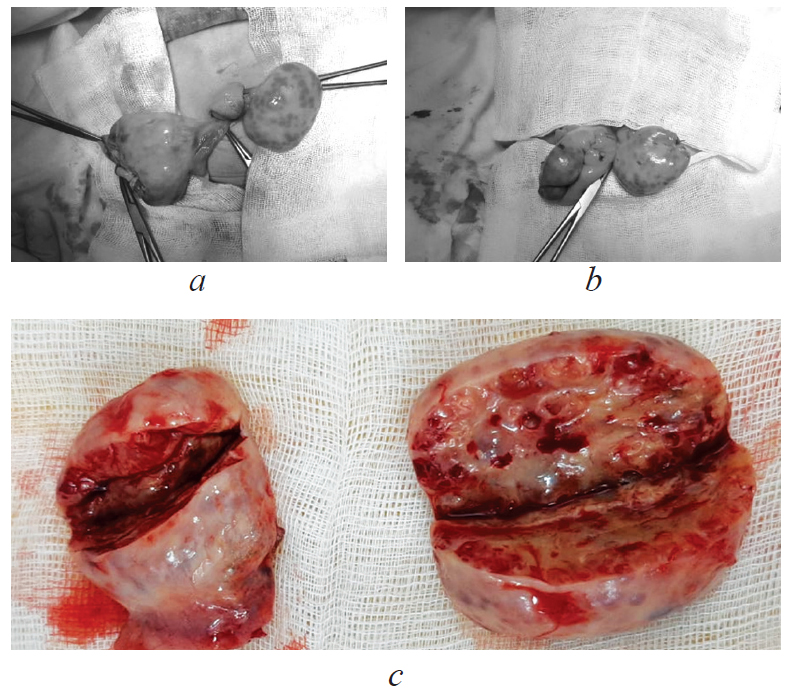

Under aseptic conditions with endotracheal anesthesia, supraumbilical minilaparotomy was performed, with ovarian cyst puncture on the right and resection of both ovaries (Fig. 3). Laparoscopic hernioplasty and umbilical hernia repair were also performed.

Fig. 3. Surgical treatment: a, b — resection of the right ovary; c — macropreparation, resected ovaries

Рис. 3. Хирургическое лечение: a, b — резекция правого яичника; c — макропрепарат, резецированные яичники